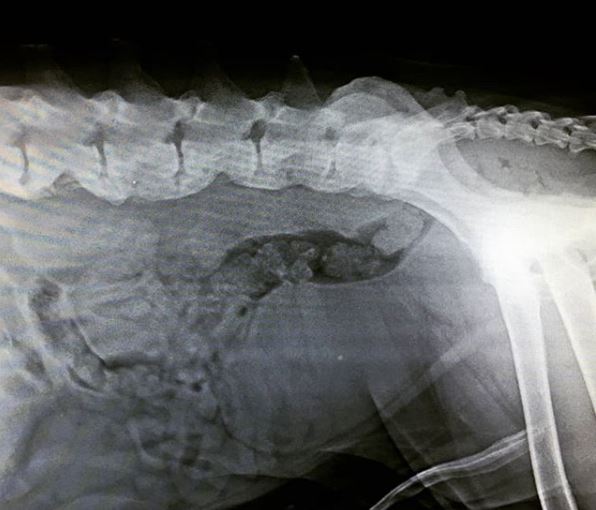

FCoV (+) çıkan kedinin nekropsisi

Halsizlik istahsızlık problemiyle gelen kediye yapılan muayene ve testler sonucunda karaciğer yetmezliği saptanmıştır. FCoV Ag/ Ab Quick test sonucu ikiside pozitiftir. Yapılan nekropside asites, sarılık, […]